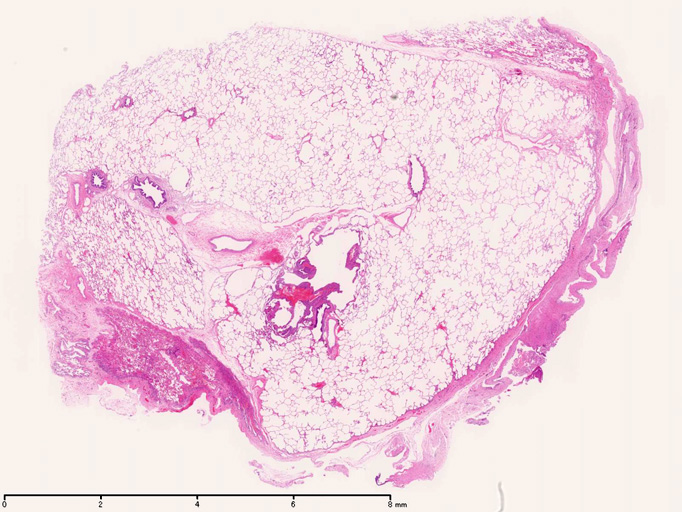

LAMの組織病理

LAMの肺病変

嚢胞周囲または肺血管, リンパ管, 細気管支にそうLAM cellの浸潤, 集簇を特徴とする。LAM cellには2種類が認められ, 小型紡錘形細胞と細胞質の豊富な類上皮様細胞があり, 紡錘型は主に集簇巣の中心に存在し増殖能が高い。 類上皮様LAM cellは辺縁部に多く, 増殖能は低いがHMB45を強く発現している。

LAM cellの免疫染色--SMA, desmin, vimentin(vimentinはいつも陽性とはならない)が陽性となりmuscle lineageであるが典型的な筋細胞と異なり,

嚢胞形成はLAM cellの増殖と関連しており, 細胞が産生するmatrix metalloproteinases(MMPs)による組織破壊によるらしい。